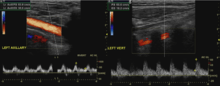

Diagnostic tests